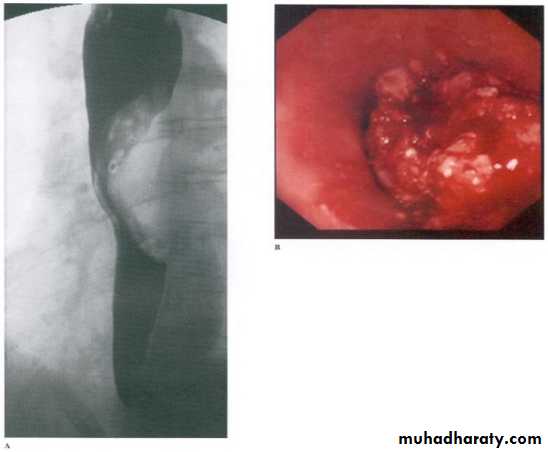

Malignant stricture

CA esophagus is the cause for the malignant stricture

The most common types of esophageal carcinoma are squamous cell carcinoma and adenocarcinoma .

esophagography is unique among esophageal studies for assessing both morphology and motility. Barium esophagography remains the study of choice for characterization of esophageal strictures. Esophageal carcinoma may demonstrate a variety of appearances on barium esophagrams.

Annular Carcinoma

Narrowing :

1-Constant.

2-Irrigular .

3-Variable length.

4- Shouldering sign.

5-Fistula (double tract).

6-Soft tissue shadow of the mass